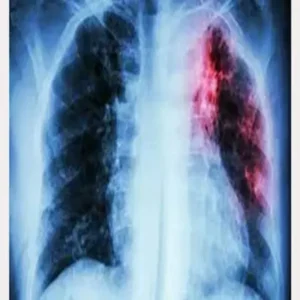

Tuberculosis – शाहजहांपुर मेडिकल कॉलेज में टीबी मरीज की दुखद मौत

Tuberculosis – मंगलवार देर रात शाहजहांपुर के राजकीय मेडिकल कॉलेज में इलाज करा रहे एक युवा टीबी मरीज की ऊंचाई से गिरकर मौत हो गई। अस्पताल प्रशासन और पुलिस के अनुसार, यह घटना अचानक हुई और पूरे परिसर में अफरातफरी मच गई। मृतक की पहचान सीतापुर जिले के मोहरनिया निवासी 25 वर्षीय अनुज कुमार के रूप में हुई है। डॉक्टरों का कहना है कि वह कई महीनों से गंभीर क्षय रोग से पीड़ित था और हाल ही में उसकी हालत बिगड़ने पर यहां भर्ती कराया गया था। यह घटना अस्पतालों में मरीजों की सुरक्षा और मानसिक स्वास्थ्य पर एक बार फिर सवाल खड़े करती है।